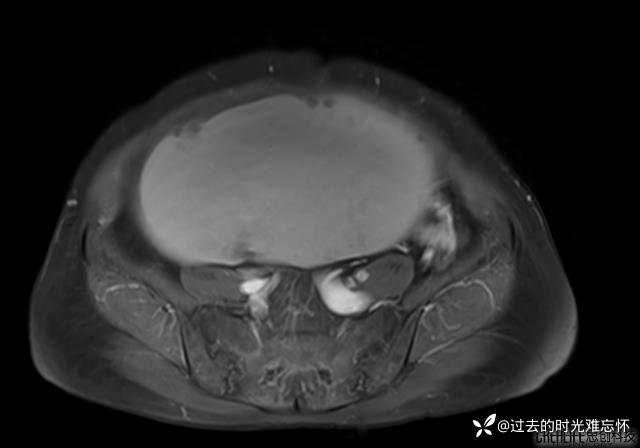

患者性别:女

患者年龄:65岁

主诉: 发现腹部隆起半年余。无其他明显不适。

浆液性囊腺瘤 (22)